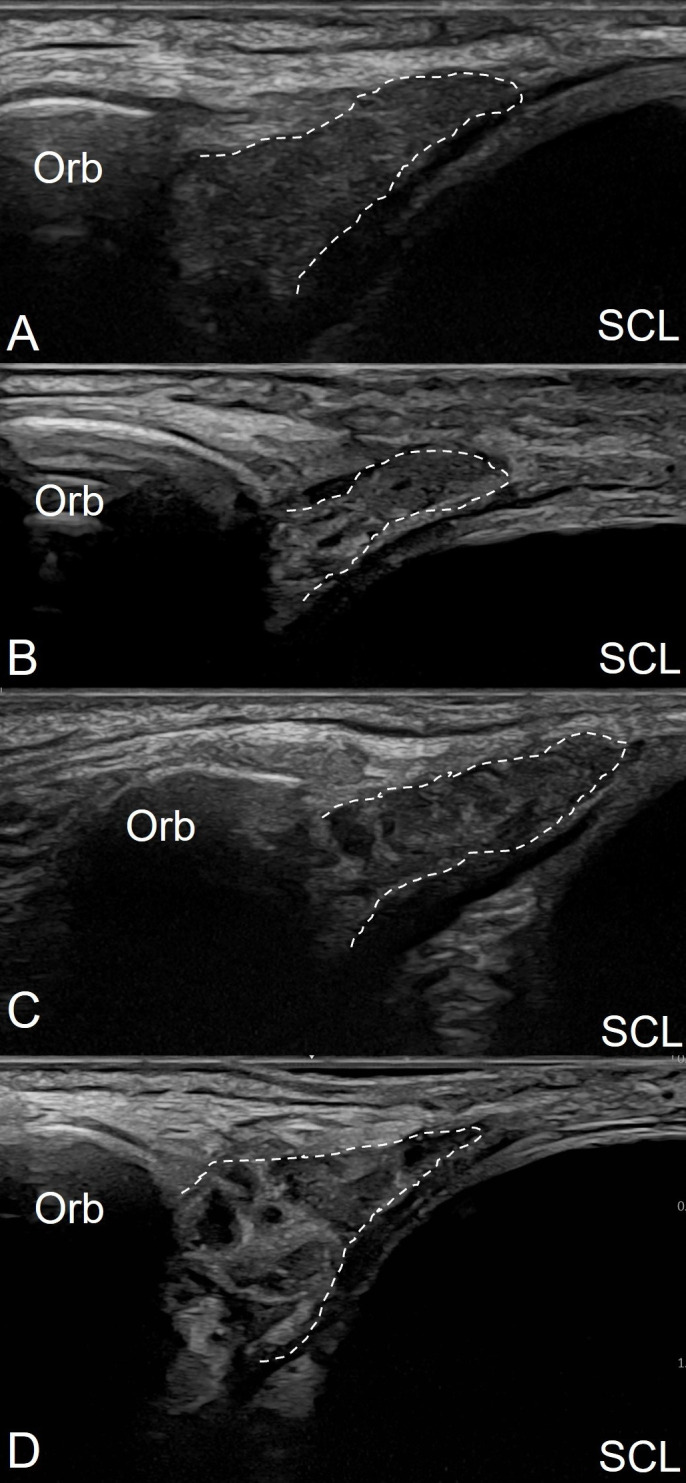

Methods: Patients with suspected pSjD, evaluated by salivary gland ultrasound (SGUS) and lacrimal gland (LGUS) as part of the diagnostic set-up were included. All had unstimulated sialometry, Schirmer's test and laboratory test done (including autoantibodies). Ultrasound examination was performed with a GE Logiq E10 (a linear 4-20 MHz transducer for SGUS and a 6-24 MHz hockey stick transducer for LGUS). The OMERACT consensus-based greyscale scoring system (0-3) for salivary glands was applied for all glands. A score of ≥2 was considered pathological.

Conclusion: LGUS has moderate sensitivity and high specificity for the diagnosis of pSjD. The OMERACT scoring system appears relevant for scoring pathology in the lacrimal glands using grade ≥2 as cut-off and may be a valuable supplementary tool for diagnostic evaluation in pSjD.